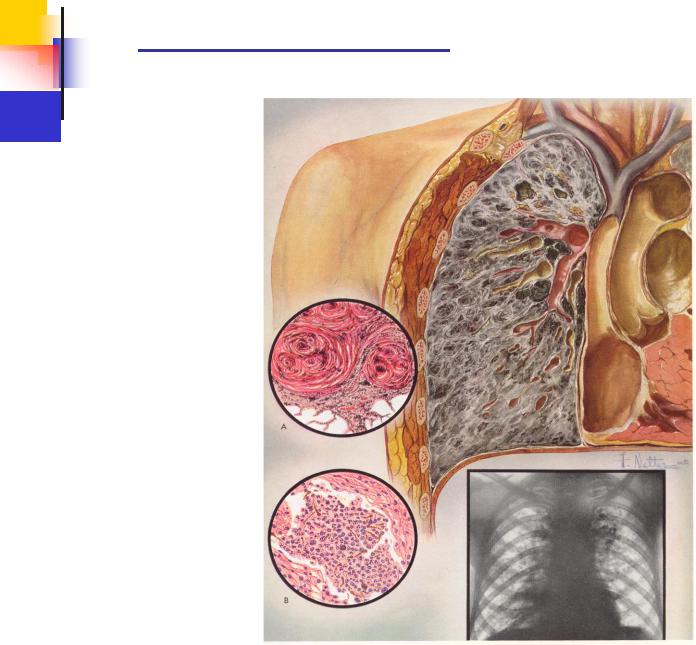

Силикоз входит в ряд профессиональных заболеваний органов дыхания. Это одна из разновидностей пневмокониозов, возникает от длительного вдыхания производственной пыли с содержанием высокой дозы свободной двуокиси кремния.

Опасность представляют небольшие, до 3-5 нм микрочастицы кварца, кристобалита. Когда допустимая концентрация вредных веществ в воздухе превышена, происходит оседание мелкодисперсной пыли на бронхах и альвеолах легких.

Какую форму принимает патология, зависит от времени воздействия промышленной пыли, ее интенсивности, общего состояния организма и наличия сопутствующих заболеваний. Клинико-морфологические формы силикоза определяют как:

- узелковые;

- рассеянно-склеротические;

- комбинированные.

По характеру изменений различают узелковый, интерстицнальный и узловой пневмофиброз. Диффузно-склеротическая форма пневмокониоза рентгенологически характеризуется преобладанием интерстициальных, пернваскулярных и перибронхиальных изменений. Поражения иитерстициального характера обычно диффузные, двусторонние. Узелковому пневмокопиозу свойственны мелкие затемнения в легких, являющиеся отображениями кониотических узелков. Узелки обычно имеют округлую форму, среднюю интенсивность и четкие контуры.

В соответствии с рентгенологическими проявлениями различают I, II и III стадию пневмокониоза. При определении стадии пневмокониоза учитывают размеры, распространенность и количество узелков и узлов, а также степень выраженности иитерстициалыюго фиброза.